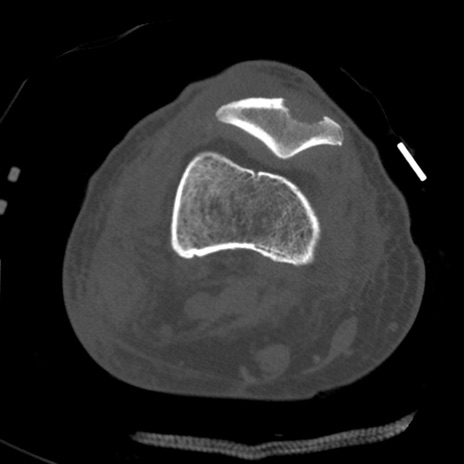

症例28 右膝関節CT(横断像)

右膝関節CT